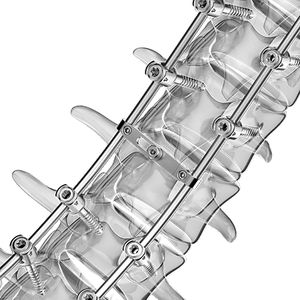

... bloqueo, vástagos de diferentes formas y tamaños. Los implantes mont blanc MIS se pueden combinar para crear un sistema de implante posterior de la columna vertebral en un abordaje mínimamente invasivo y/o un abordaje ...

... la varilla elegida, se añaden estructuras con mayor o menor reparto de la carga. Por consiguiente, la implantación de un sistema de este tipo es reversible. Las varillas de conexión de material polimérico imitan los ligamentos naturales ...

... El sistema Phoenix permite la fijación híbrida con los otros componentes a través de placas y barras longitudinales, asegurando la estabilidad y la fusión occipito-cervical. ...